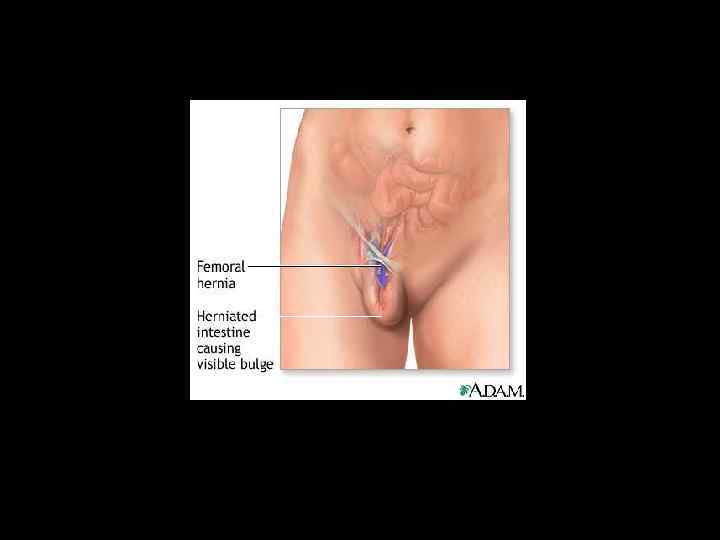

БЕДРЕННАЯ ГРЫЖА